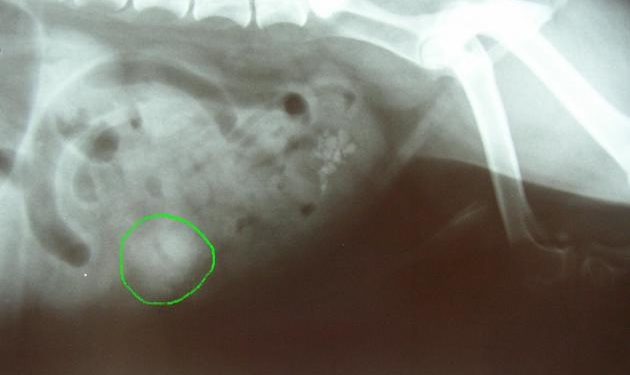

Comment diagnostiquer une occlusion intestinale ?

Le diagnostic clinique d’occlusion intestinale repose sur l’association de 4 signes : douleur abdominale, arrêt des matières et des gaz, nausées ou vomissements, météorisme abdominal. Le signe le plus spécifique est l’arrêt du transit et notamment des gaz.